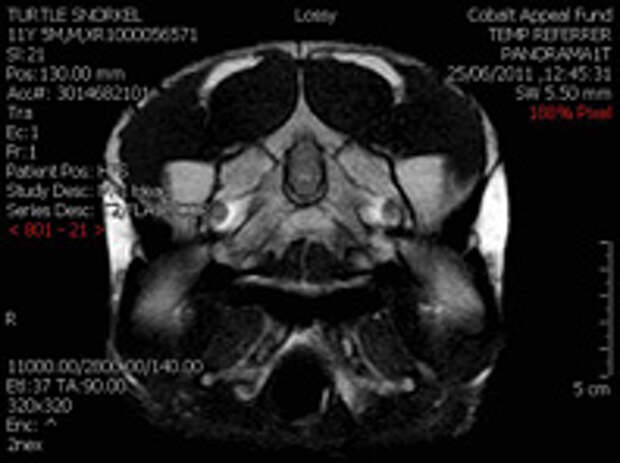

Данные веществ способны предотвратить развитие эпилепсии. Напомним: при эпилепсии активность нейронов в головном мозге нарушена. Некоторые из них слишком активны, что вызывает эпилептические приступы.

Сотрудники Университета Луизианы определили, в каких именно нейронах происходит сбой, нашли и запатентовали соединения, известные как LAU.

Шипики образуют синаптические соединения нейронов - связки, помогающие клеткам общаться. Более того, соединения восстанавливали плотность шипиков и не давали образовываться аномальным шипикам. Позитивное влияние соединений, как сообщается, сохранялось сроком до 100 дней. По сути, развитие эпилепсии было остановлено.